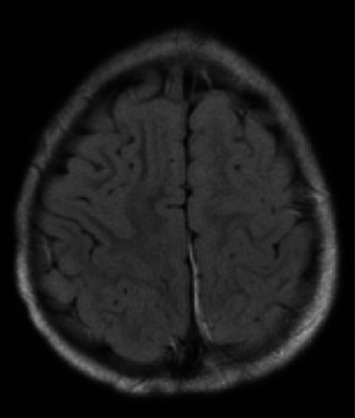

Sturge-Weber Syndrome (SWS), also called encephalotrigeminal angiomatosis, is a rare congenital neurological condition classified by the hallmark findings of a port-wine birthmark, leptomeningeal angiomas, and glaucoma. Here, we present a case of a two-year-old patient with a history of a left-sided port-wine birthmark involving the V1-V2 dermatomes who re-presented to the emergency department with focal right-sided seizure-like activity in the setting of a recent head trauma. The patient was admitted for further workup, where video electroencephalography demonstrated the presence of electrographic seizures developing from the left posterior quadrant, with continuous focal slowing over the left hemisphere, and with magnetic resonance venography revealing findings concerning for a pial angiomatosis. This finding, coupled to new-onset seizure-like activity in a patient with a port-wine birthmark, supported a diagnosis of SWS. He was started on an antiepileptic drug regimen with resolution of seizure-like activity while inpatient and his subsequent care was transferred to a specialized clinic designed to manage patients with SWS. Most patients diagnosed with SWS exhibit seizure-like activity, often presenting as infantile spasms, within the first year of life; our patient, on the other hand, began to exhibit focal seizures following a traumatic event and was later found to harbor findings consistent with SWS. Overall, this case highlights the role of a multidisciplinary team in the management of patients with SWS and demonstrates the importance of routine follow-up testing, imaging, and subspecialty care for these patients.